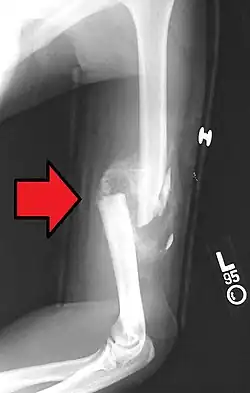

- Die winkelstabile Platte am proximalen Humerusschaft

-

Eine Fraktur am oberen Ende des Humerus -

Versorgung mit winkelstabiler Platte -

Ansicht in anderer Ebene